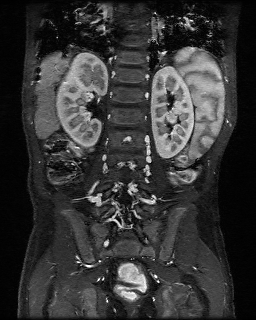

3. Feng, L., Grimm, R., Block, K. T., Chandarana, H., Kim, S., Xu, J., Axel, L., Sodickson, D. K. and Otazo, R. (2014), Golden-angle radial sparse parallel MRI: Combination of compressed sensing, parallel imaging, and golden-angle radial sampling for fast and flexible dynamic volumetric MRI. Magn Reson Med, 72: 707–717. doi: 10.1002/mrm.24980

This work aimed to develop a fast and flexible free-breathing dynamic volumetric MRI technique, called iterative Golden-angle RAdial Sparse Parallel MRI (iGRASP). Feng and colleagues combined compressed sensing, parallel imaging, and golden-angle radial sampling to improve clinical studies that require robustness to motion and simultaneous high spatial and temporal resolution. iGRASP has been shown to achieve higher acceleration capability than either parallel imaging or coil-by-coil compressed sensing alone. The technique was used in clinical applications, such as free-breathing dynamic contrast-enhanced imaging in the abdomen of both adult and pediatric patients, and in the breast and neck of adult patients.